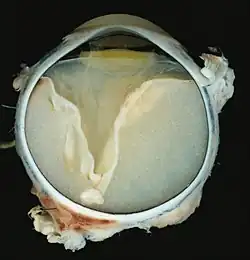

- Pathologische Präparate beim Morbus Coats

V-förmige Ablösung der Netzhaut durch das Exsudat. -

Vollständige Ablösung der Netzhaut durch das Exsudat.

Eine ausgeprägte Netzhautablösung und ein gelbliches Exsudat unter der Netzhaut, das Cholesterinkristalle enthält, sind charakteristisch für den pathologischen Befund.

Unter dem Mikroskop kann die Wand der Netzhautgefäße in manchen Fällen verdickt, in anderen ausgedünnt erscheinen. Hinzu kommt eine unregelmäßige Erweiterung der betroffenen Gefäße.[25] Charakteristisch ist ein Exsudat, das sowohl aus Cholesterinkristallen, mit Cholesterin und Pigmenten beladenen Makrophagen, als auch aus roten Blutkörperchen und Hämosiderin besteht.[26] An der Netzhaut können sich eine durch das Exsudat ausgelöste granulomatöse Reaktion und in manchen Fällen auch eine durch die Verletzung ausgelöste Gliose finden.[27]